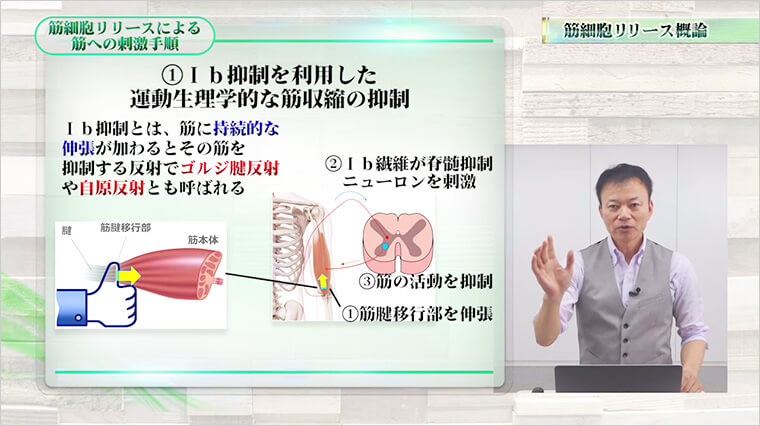

- 治療効果を2倍、3倍とUPさせる!軽い圧を5回かけるだけで、緊張してこり固まった筋肉をユルンユルンにする“Ib抑制”とは?

緊張してこり固まった筋肉…あなたはどのように対処していますか?もし、筋肉を緩めることなく治療を始めているのであれば要注意。なぜなら、筋肉がこり固まった状態では、治療効果が弱まってしまうからです。ここでお伝えする“Ib抑制”を取り入れれば、あなたの治療効果を2倍も3倍も引き上げることが可能になります。